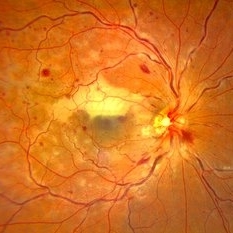

BRAO (3 files)

BRAO (3 files)

BRAO (3 files)

BRAO (3 files)

BRAO with CRVO (1 file)

BRAO with CRVO (1 file)